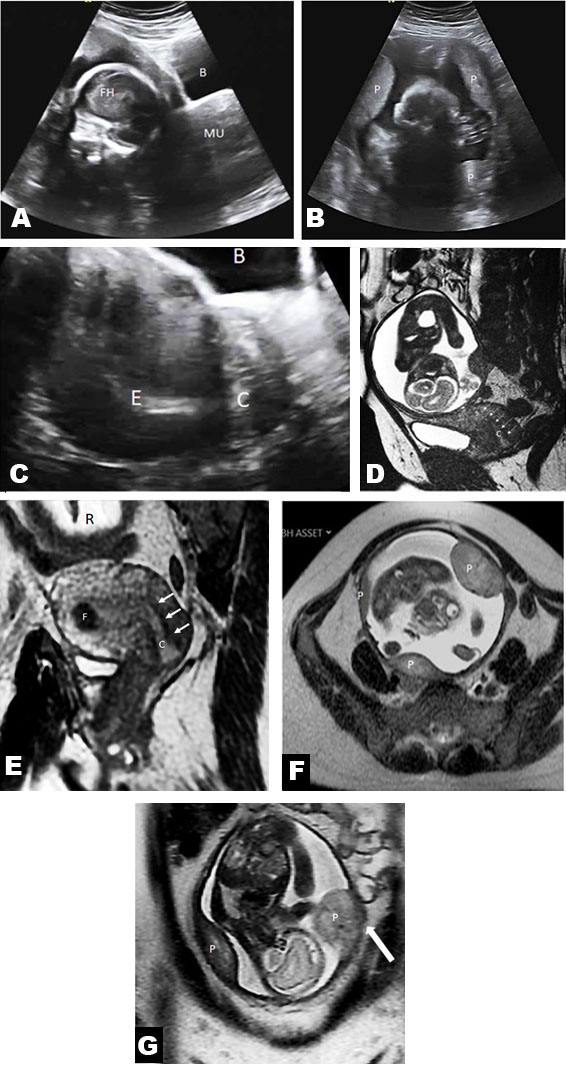

A gravid uterus and a single cervix were identified on physical examination. Repeat US showed an empty left uterine horn with normal cervix, and a separate pregnancy of uncertain anatomic location in the right pelvis. An MRI was requested to clarify whether there was an abdominal or other ectopic pregnancy, or a uterine anomaly. Magnetic resonance imaging on a 1.5 Tesla superconducting magnet revealed an empty left unicornuate uterus with a single cervix. The right rudimentary horn contained a 25-week live gestation. There were 4 separate placental lobes with multifocal abnormally invasive placenta (both placenta increta and percreta). No polyhydramnios was seen. The maternal kidneys were normotopic (Figure 2).

Figure 2: 34-year-old female with gravid non-communicating rudimentary horn in a unicornuate uterus with placenta accreta spectrum. (A) Sagittal US image at 27 weeks gestational age for size and dates revealed a live fetus on the right with a contiguous empty second uterine horn, raising the question of a duplication anomaly. Fetal head (FH), main uterine horn (MU), bladder (B). (B) Transverse US image shows multiple separate placental units (P). (C) Sagittal US scan through the main uterine body shows empty endometrial lining. Only this single cervical canal could be visualized in this patient. Bladder (B), endometrial lining (E), cervix (C). (D) 1.5 Tesla MRI (Signa superconducting magnet, GE healthcare, USA) sagittal 2D fiesta (TR:4.27 TE:1.83 ms, 5 mm slice thickness) shows gravid rudimentary horn contiguous with the endocervix of the main uterine body. This image could easily be misinterpreted to mean that the pregnancy communicates the cervical canal shown here. In fact, this cervical canal belongs to the main uterine body and not the rudimentary horn. There is no natural route of egress for this fetus. Cervical canal (C), arrows). (E) Off axis coronal T2 FRFSE (breath held ASSET, TR 2000 TE:87.5 ms, slice thickness 5 mm) along the long axis of the main uterine horn clearly demonstrates that the only cervical canal (arrows) belongs to the main uterine body (and not to the pregnant rudimentary horn). Incidental note is made of an intramural fibroid in the upper right uterine body (F). Gravid rudimentary horn (R). (F and G) Axial (F) and coronal (G) MRI scans (breath held ASSET, TR:1065 TE: 87.6 ms, slice thickness 5 mm) demonstrate multiple separate placental units (P). There is placenta accreta (white arrow) at the left lateral margin of the rudimentary gravid horn with invasion into the myometrium extending just beyond the serosal margin of the uterus that was confirmed at delivery.